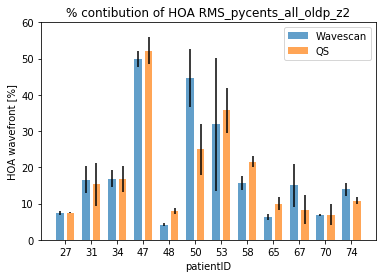

PurposeUncorrected Refractive Errors (UREs) is a reversible condition that can be treated with appropriate eyeglasses. UREs affect over 1 billion people globally, with 90% of this population living in low-and-middle-income countries where vision exams can be highly inaccessible due to a shortage of experienced eyecare professionals. This work aims to assess if a machine learning (ML) approach, when applied to data obtained with an affordable handheld autorefractor, could increase access to clinical-quality subjective refraction (SR) when operated by non-experts. MethodsData used for this analysis was obtained from a clinical study performed at Aravind Eye Hospital in Madurai, India, using a low-cost portable wavefront aberrometer, an early prototype of the QuickSee (QS) (PlenOptika, Inc., USA). A total of 669 participants were enrolled with ages ranging between 15 and 70 years (35.2 ± 13.7) and spherical equivalent error between -6.0 D and 3.5 D (-0.7 ± 1.67 D). Four ML regressor models were trained and tested for each power vector M, J0 and J45: random forest (RF), gradient boosting (GB), extreme gradient boosting (XGB), and a custom assembly model (ASB) that averages the predictions of RF, GB, and XGB. Algorithms were trained on a dataset of 1,244 samples using as input features: age, gender, Zernike coefficients up to 5th order, and measurement quality related metrics provided by the autorefractor. A smaller subset of 518 unseen samples was used to test the agreement of the predictions against SR using Bland-Altman analysis, overall prediction error in terms of mean absolute error (MAE) and root mean squared error (RMSE), and the percentage of agreement for 0.25 D and 0.5 D thresholds. ResultsAll models improved the agreement with SR compared to the baseline autorefraction, but ASB obtained the best results (Table 1). Bland-Altman analysis showed a decrease in the 95% limits of agreement of ±0.63 D, ±0.14 D, and ±0.08 D for M, J0 and J45, respectively. The wavefront-aberrometry related variables had the biggest impact on the prediction, while demographic and measurement quality-related features showed a heterogeneous but consistent predictive value. ConclusionsThese results suggest that ML is effective for improving precision in predicting patient’s SR from objective measurements taken with a low-cost portable device. |

Purpose : A pilot study to assess the measurement of both low- and high-order ocular aberrations from a low-cost portable wavefront aberrometer. |